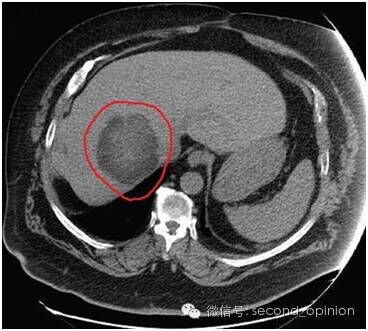

尖端放疗技术EDGE成功治疗巨大肝肿瘤脑转移患者 胰腺癌

胰腺癌尖端放疗技术EDGE成功治疗巨大肝肿瘤脑转移患者

肝癌(liver cancer)是我国常见恶性肿瘤之一,死亡率高,在恶性肿瘤死亡顺位中仅次于胃癌、食道癌而居第三位;在部分地区的农村中则占第二位,仅次于胃癌。据数据显示,我国肝癌患者的数量居然占到了全世界患者总数的55%,我国每年死于肝癌约11万人,占全世界肝癌死亡人数的45%。这是一个令人震惊的数字。高发病率,高死亡率,肝癌显然已经成为了严重影响我国总体